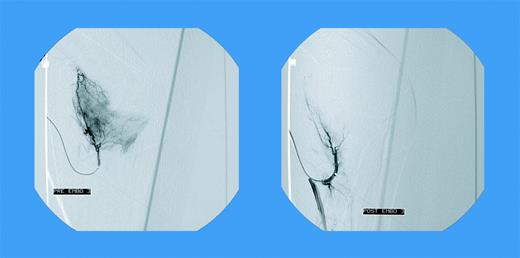

Blush in a patient with elbow bleeding. See the complete article by Mauser-Bunschoten et al, beginning on page 2654.

Selective catheterizations of the popliteal and/or the supragenual and infragenual arteries were carried out and angiograms were done with embolization performed with microcoils. Figure 1A-B dramatically demonstrates the effect of these embolizations. This holds true for either spontaneous or post–joint replacement bleeding.